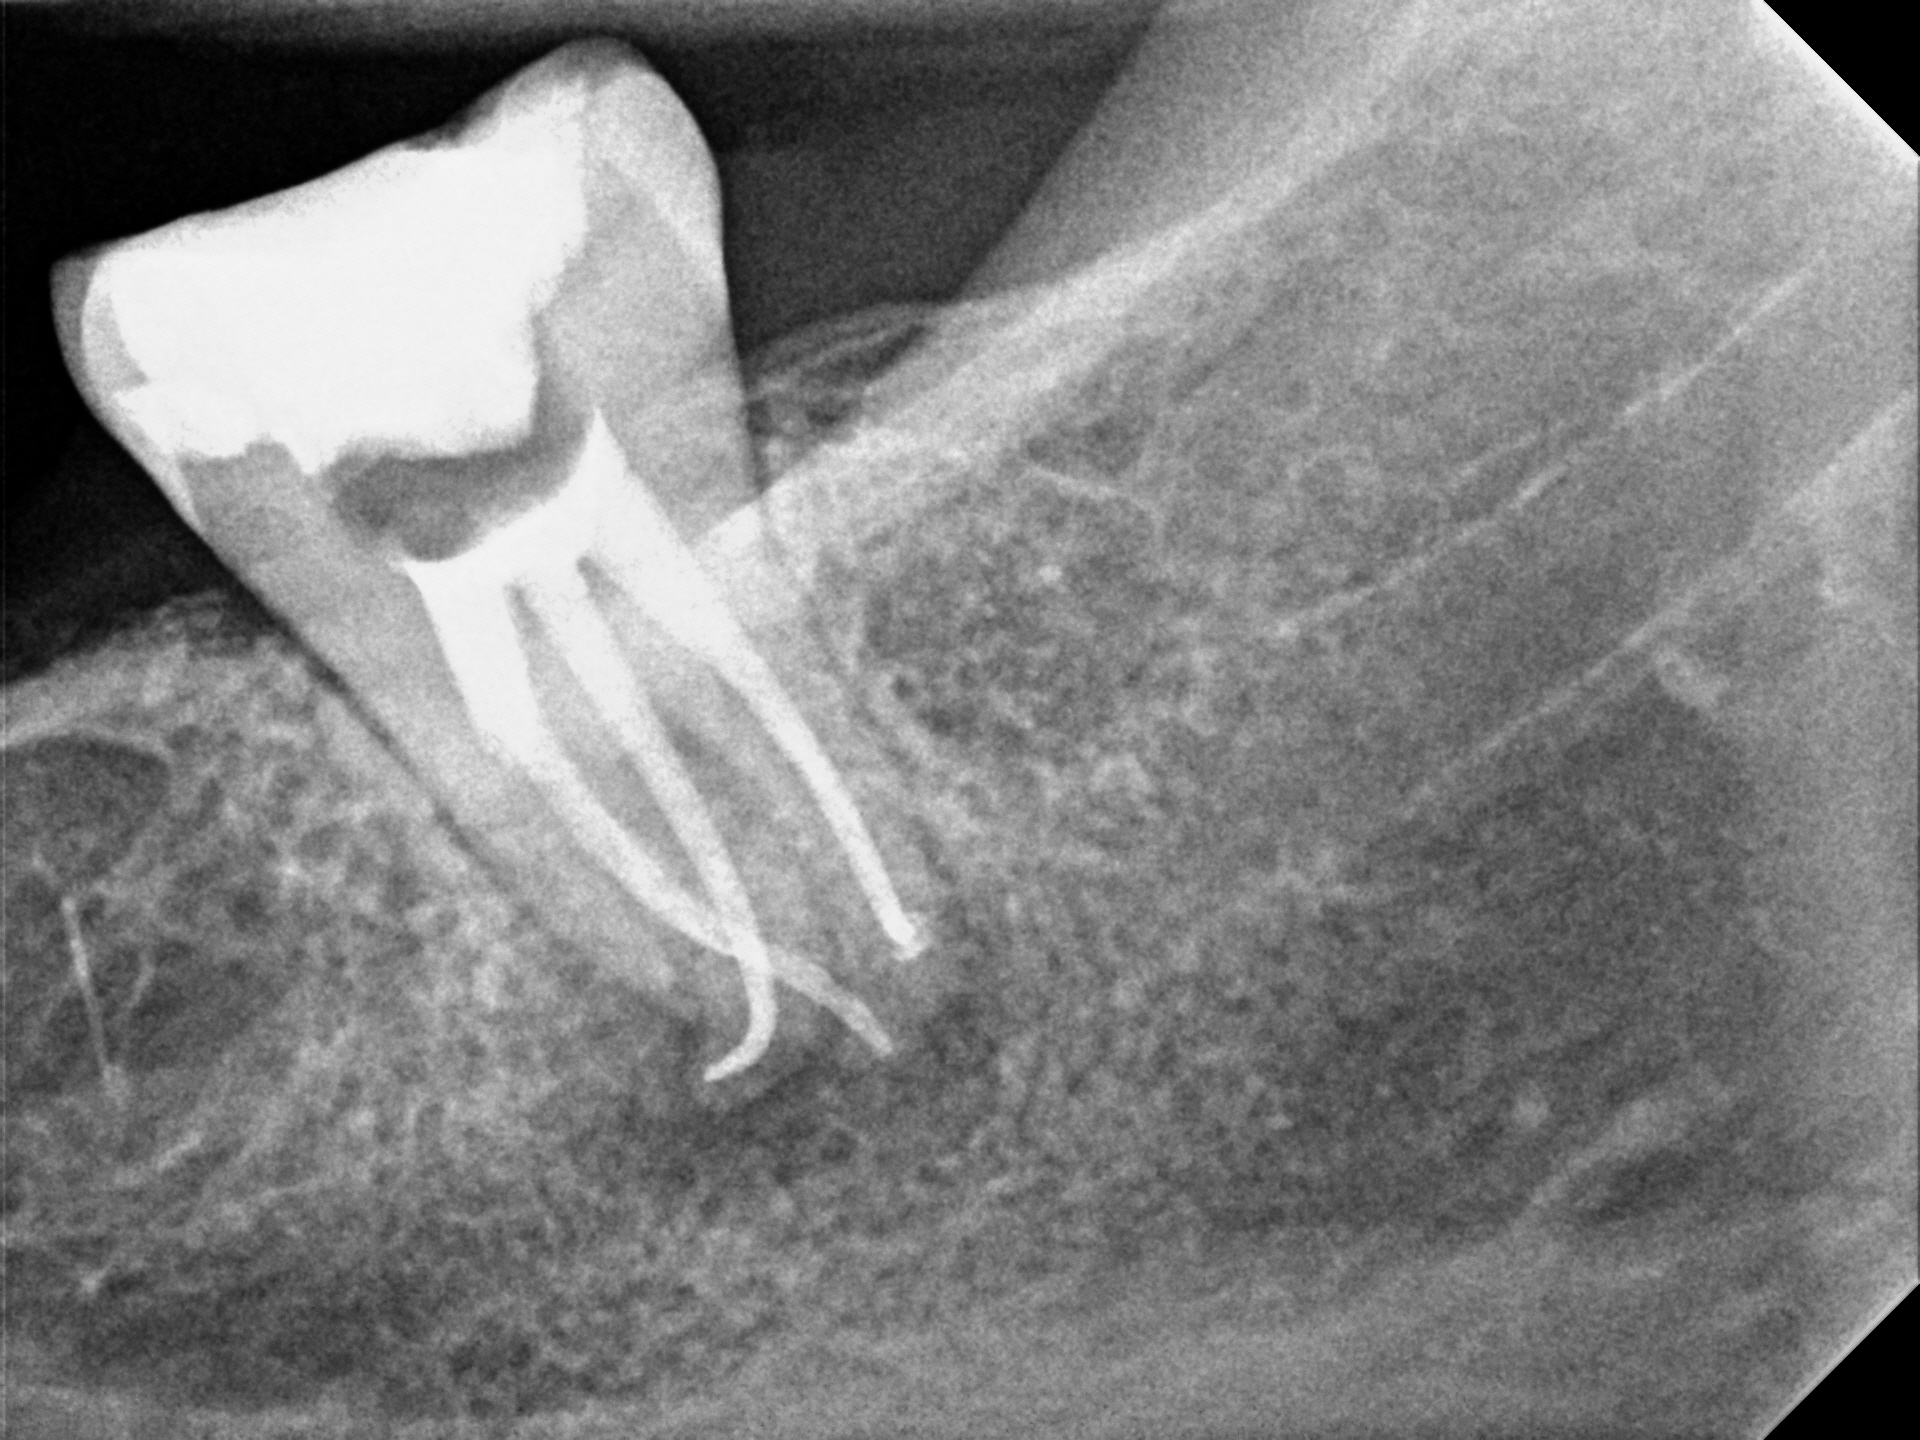

Case 9

This case shows just how curved the roots of teeth can be, which can lead to the nerve canal spaces being difficult to fully treat. These types of cases are often referred to endodontic specialists for treatment due to the added complexity of the curved roots.